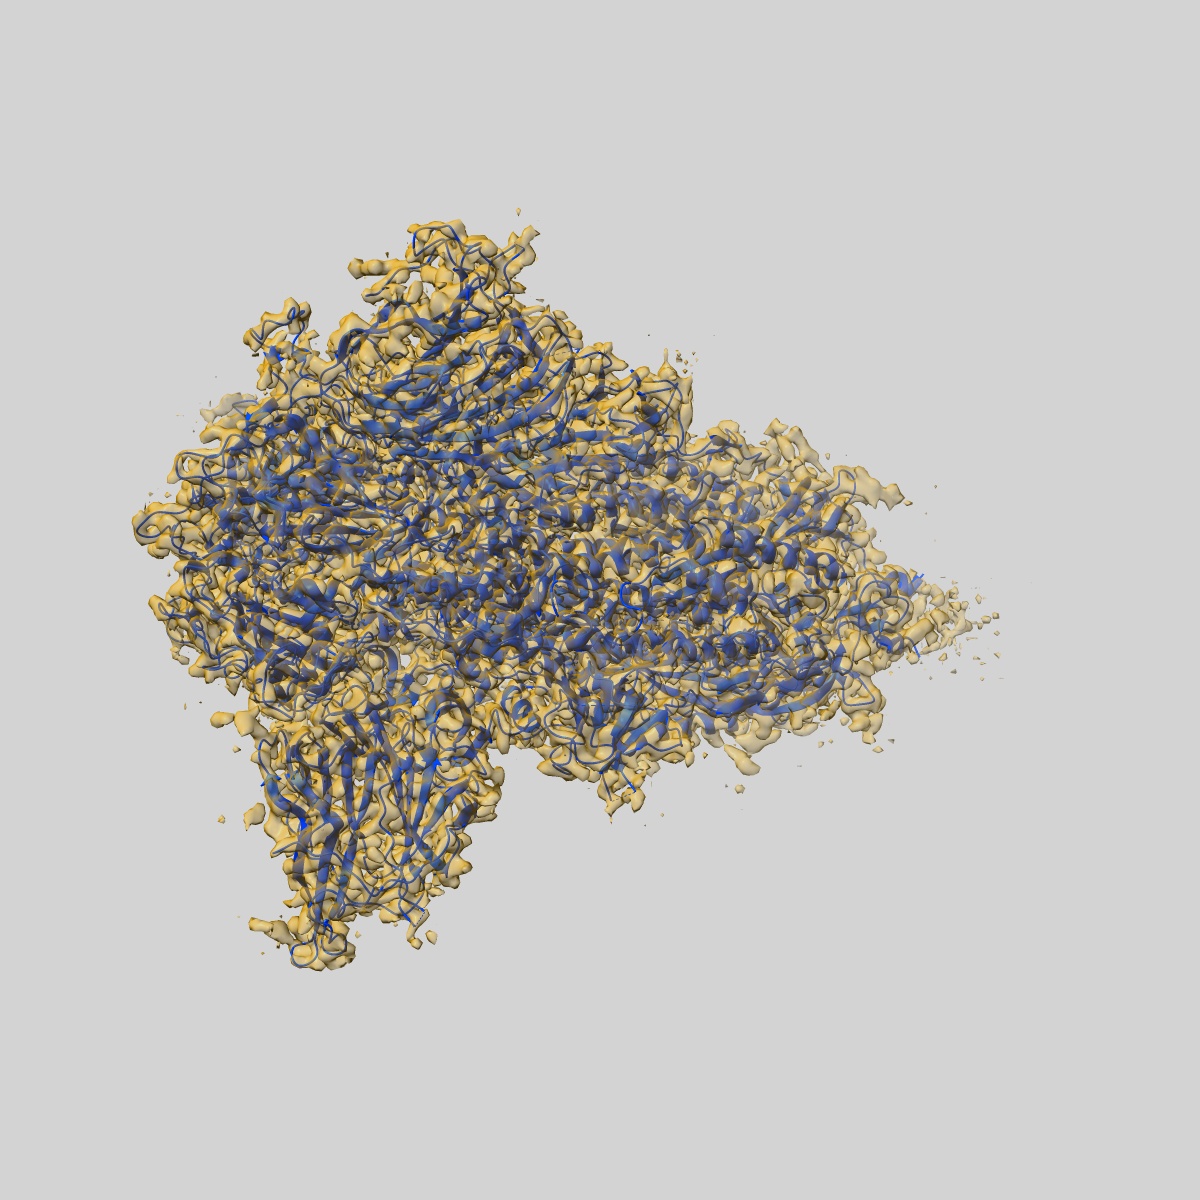

S protein of SARS-CoV-2 in the locked conformation

EMD-30889

Single-particle

2.7 Å

Sample: S protein of SARS-CoV-2 in the locked conformation

Fitted models: 7dwy

Structural basis for the different states of the spike protein of SARS-CoV-2 in complex with ACE2.

Yan R, Zhang Y, Li Y , Ye F , Guo Y , Xia L, Zhong X, Chi X, Zhou Q

(2021) Cell Res , 31 , 717 - 719